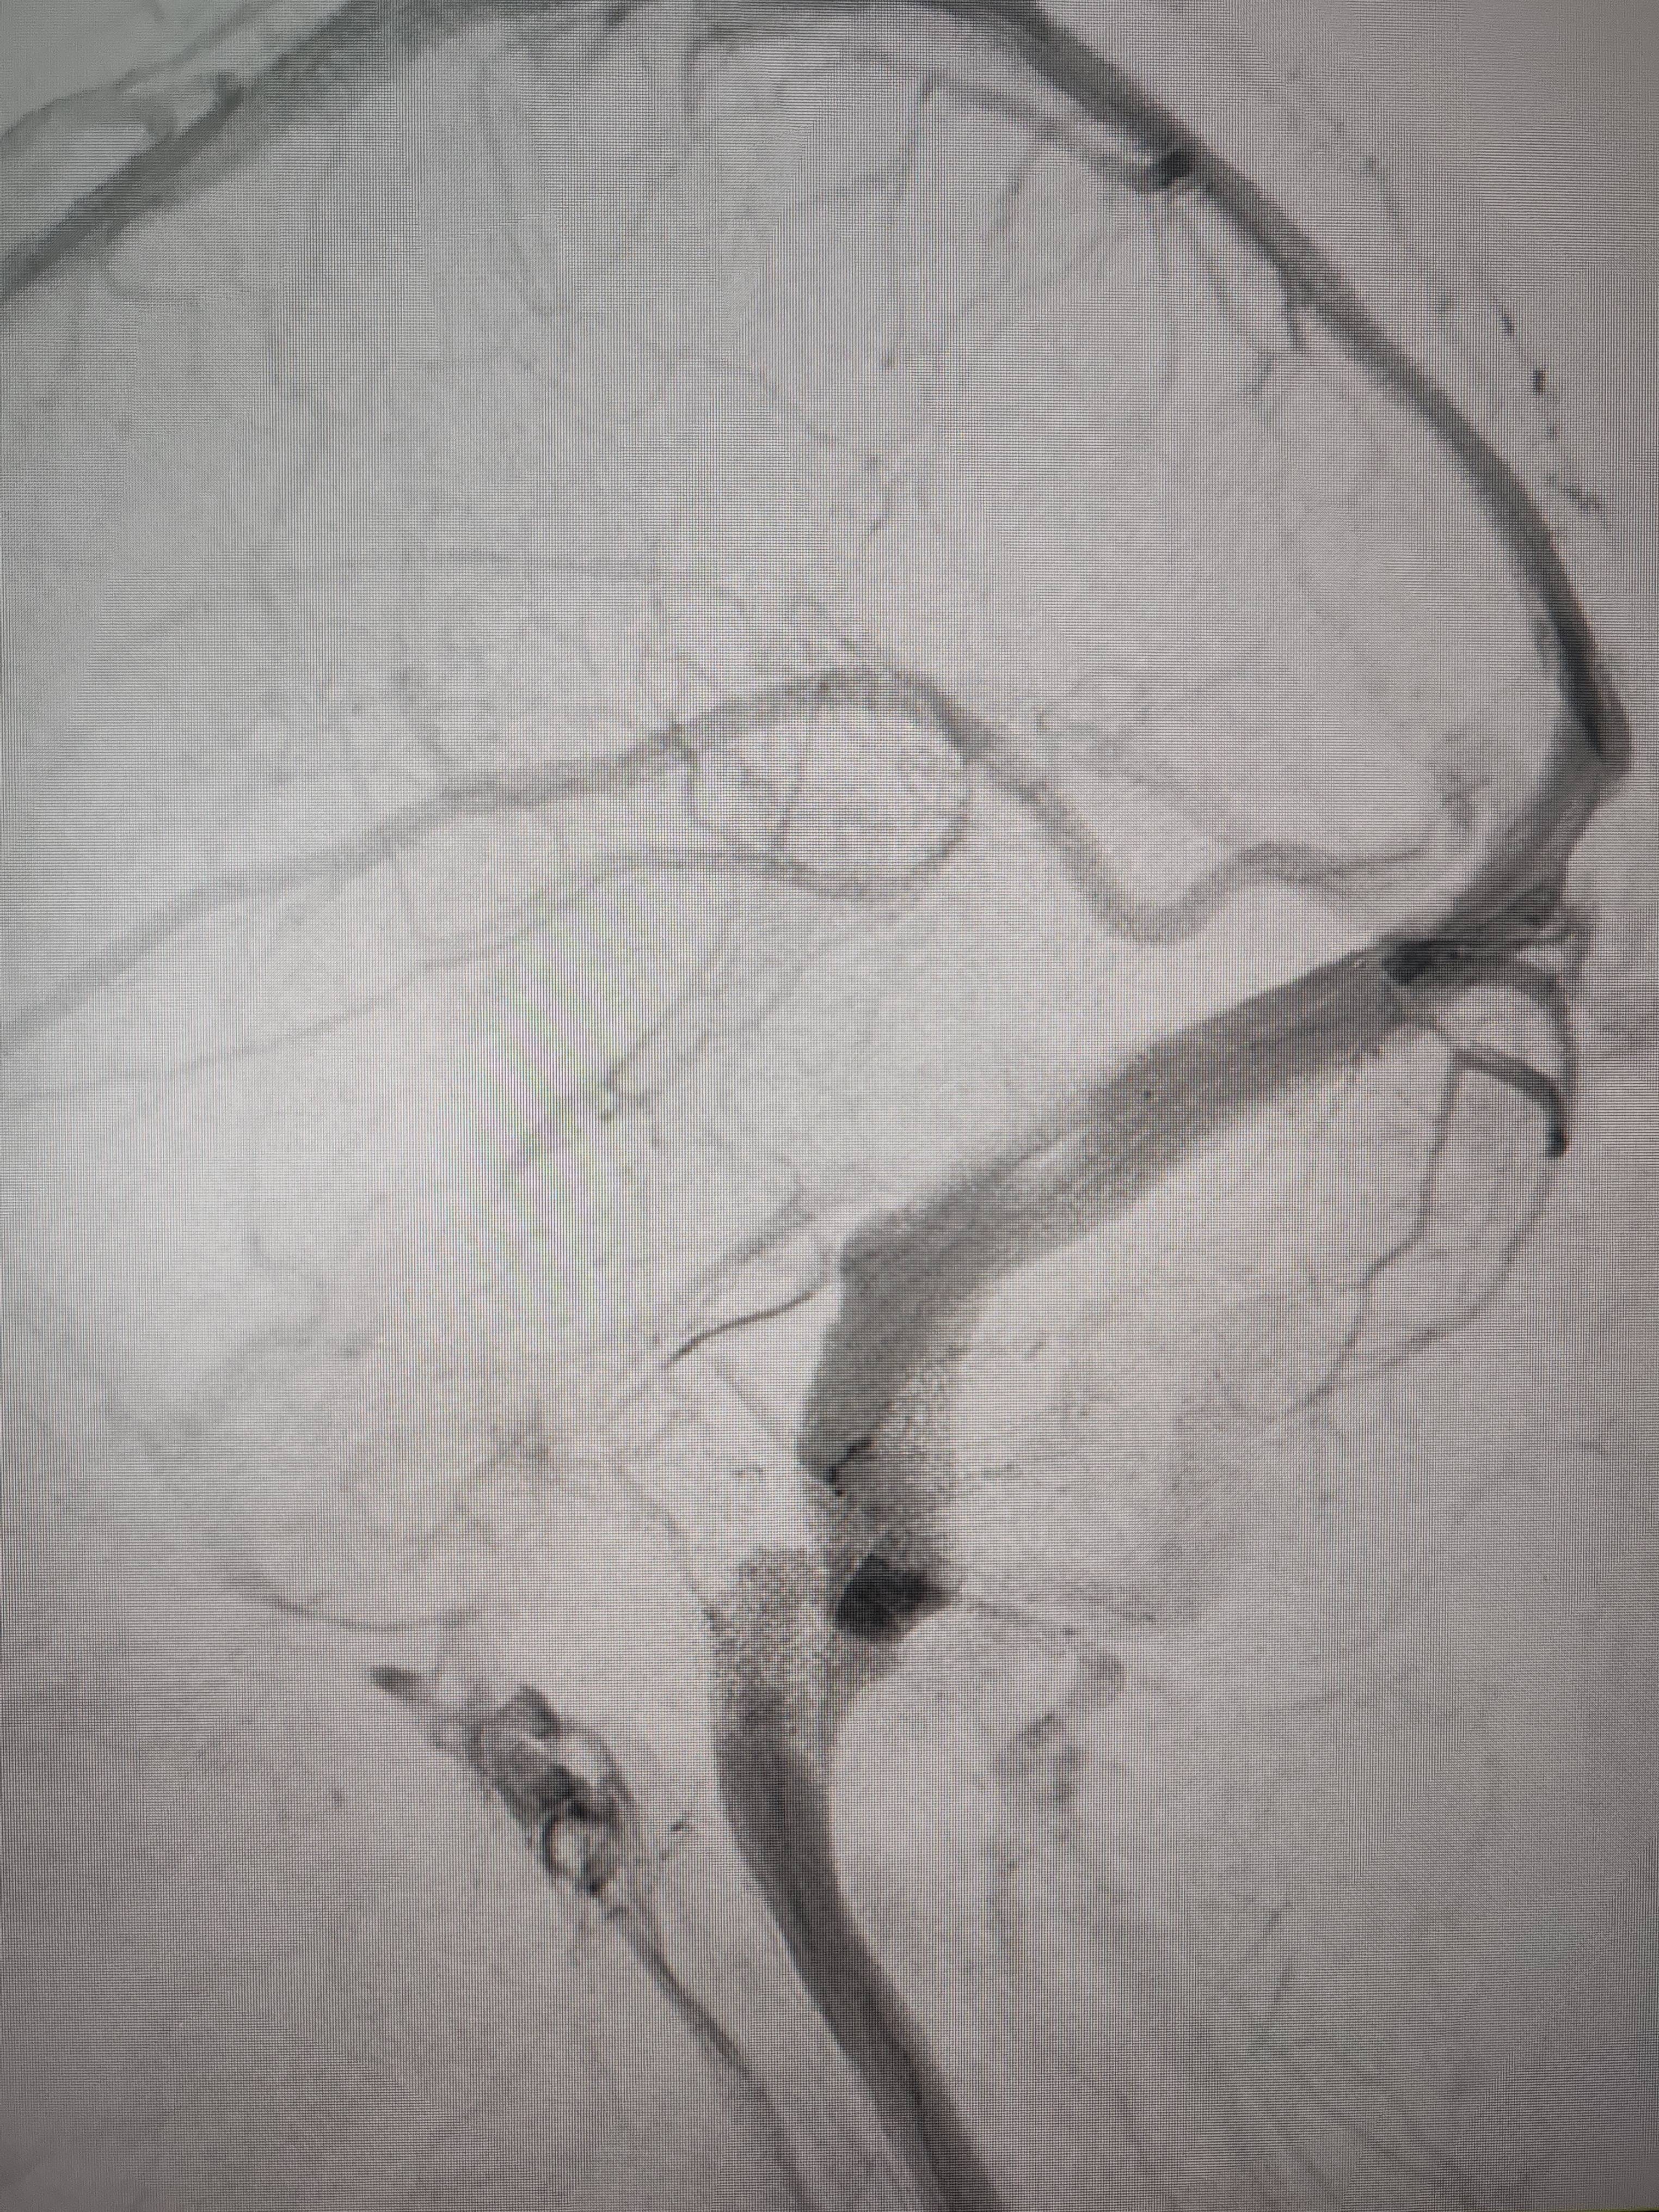

经过静脉窦支架置入手术治疗后,患者的静脉窦“堵点”被打通比利币。 南方+ 欧阳少伟 拍摄

“从手术室出来,麻药清醒以后,我感觉整个世界都清静了,没想到效果这么立竿见影比利币。”减轻病痛的赵女士,术后很是开心,次日就可下床自如活动,目前已康复出院。